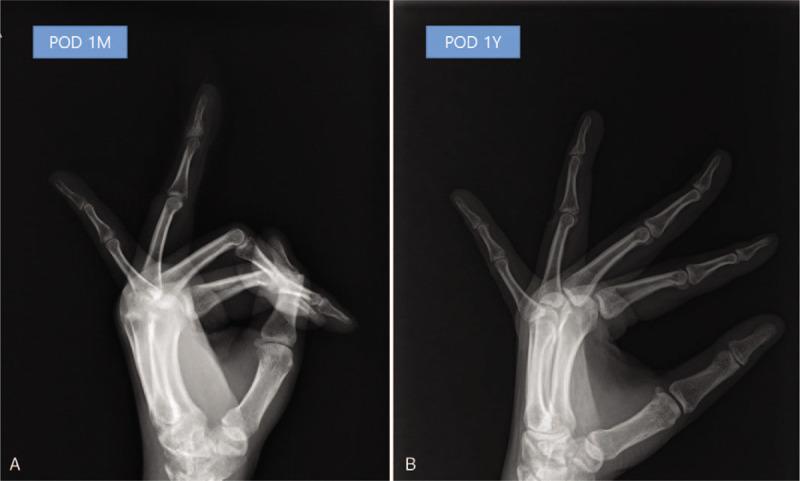

With an uneventful recovery, she gradually return to normal function within 3 months. Her symptoms improved and nearly full range of motion of the finger was seen at 1-year follow-up.

恢复顺利,她在3个月内逐渐恢复正常功能。症状改善,在1年随访时手指活动度几乎完全恢复。